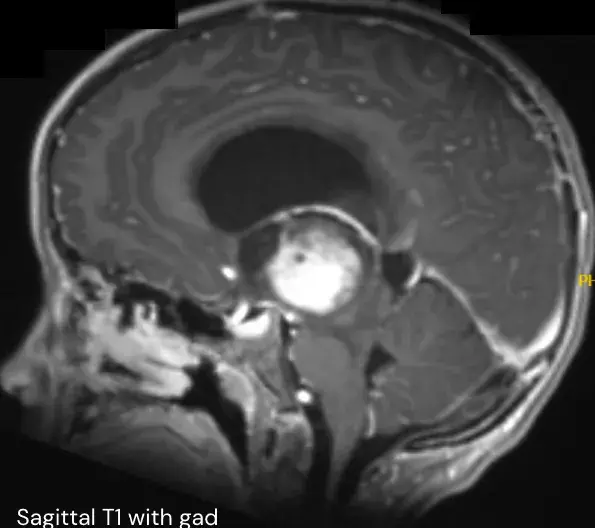

乖宝,上学要迟到了,再走快点。 爸爸,我看不清路,走不了! 一大早就急着送女儿上学的池先生听到这句话,顿时心里咯噔一下,他走到女儿面前蹲下,问她:怎么看不清?还有哪里不舒服...

医生,孩子刚才还好好的,突然就哭喊着说自己头痛,好像下一秒就要痛晕过去了一样,你快救救他!急诊室内的一幕令众人纷纷侧目,一位神色慌张的母亲正搀扶着她年幼的儿子,而这竟差点...

一年多前,10岁的安格因呕吐被查出第四脑室肿瘤,在接受分流术后的第5天,安格被再次推入手术室,成功全切了肿瘤,病理报告显示为低级别胶质瘤。然而安格一家看似有惊无险的治疗之路,...